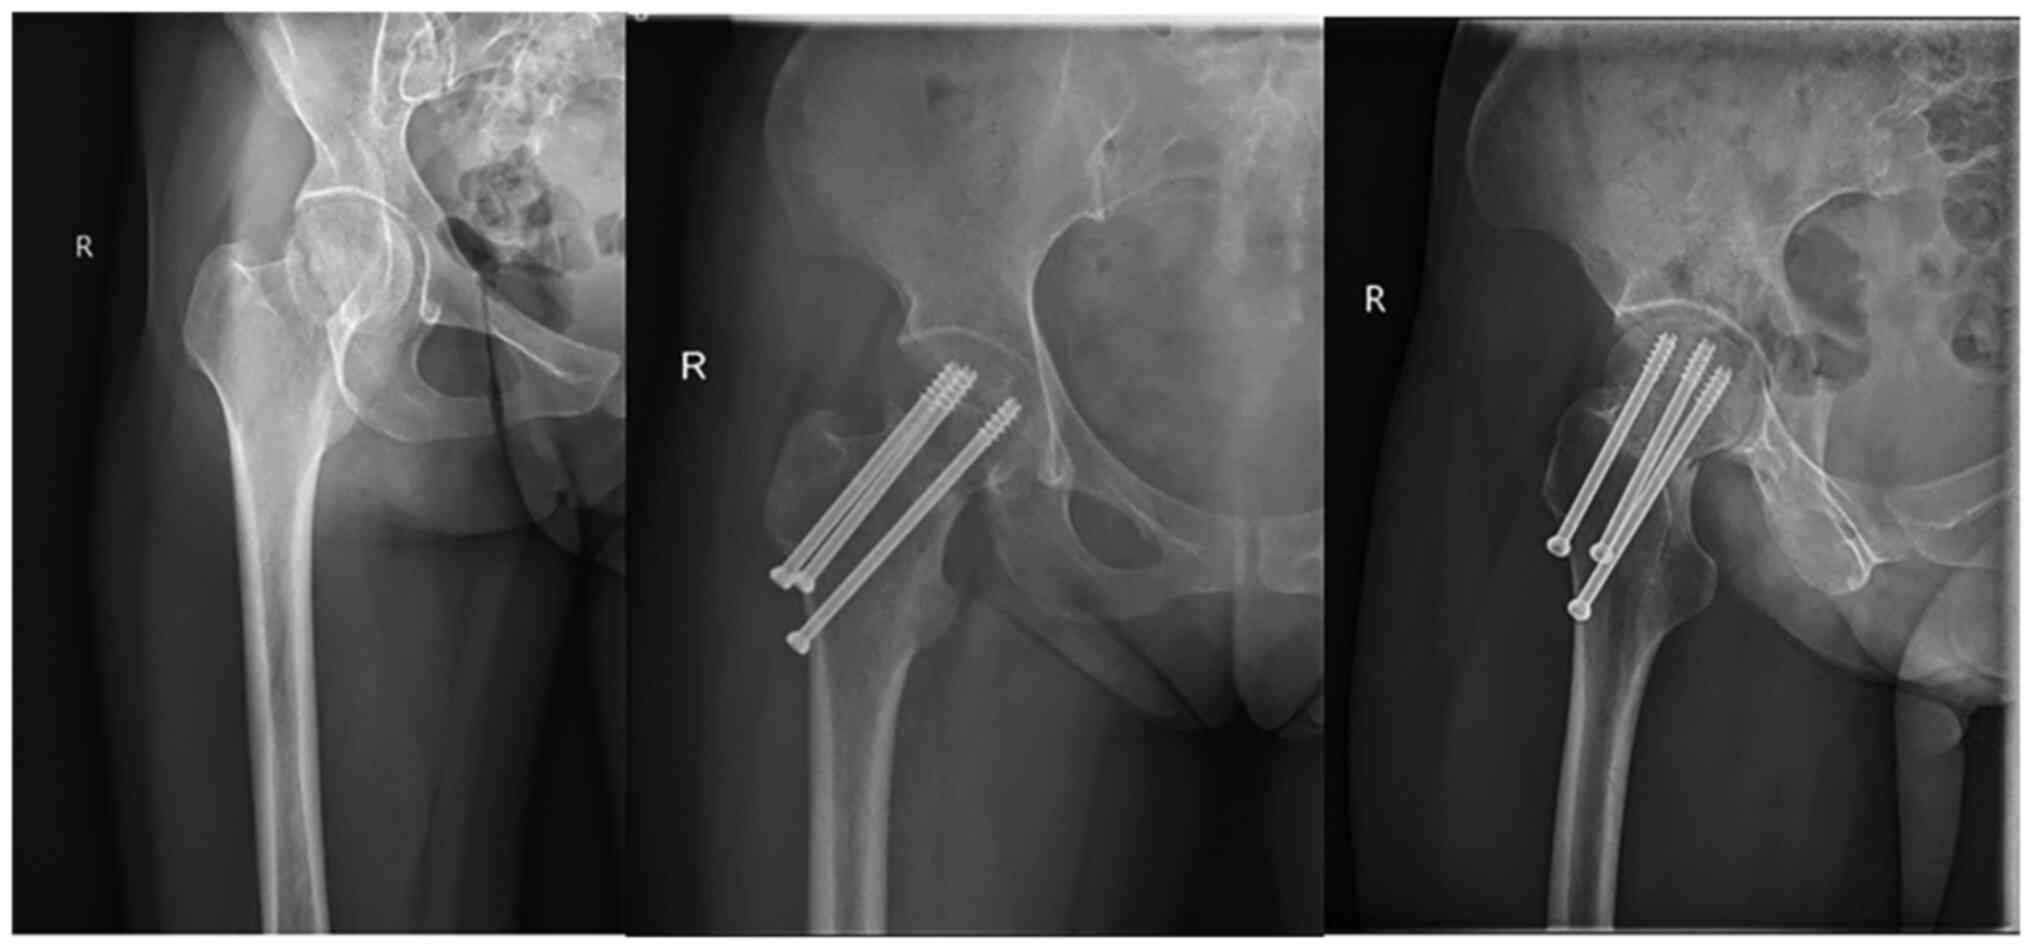

After surgery, the patients were treated with pain relief, anti-infection and anticoagulation therapies. On the second day after surgery, the patients could perform lower limb functional exercises in a sitting position. Full weight-bearing of the affected limb was avoided for three months, and gradual weight-bearing to full weight-bearing was performed with the help of a walking aid according to fracture healing during follow-up examinations. Patients in groups A and B visited the First Affiliated Hospital of Nanjing Medical University (Jiangsu Province Hospital) for regular follow-up examinations at 1, 2, 3, 6 and 12 months after surgery. At these follow-ups, anteroposterior and lateral hip radiographs (digital radiography equipment; Ysio Max Smart Speed MAX Platform; Siemens Healthineers) were performed and used to assess fracture healing, and a functional assessment of the hip joint was performed. Typical cases in both groups are shown in Figs. 1 and 2.

Figure 2

Case from group B: Li, male, 80 years old. The left panel shows the patient with a subcapital femoral neck fracture on a preoperative X-ray; the middle and left panels show the postoperative femoral neck fracture, at the last follow-up visits, at 16 and 12 months after surgery, respectively. Anteroposterior X-ray and lateral radiographs with three cannulated screws with parallel distribution demonstrate that the fracture has already healed.